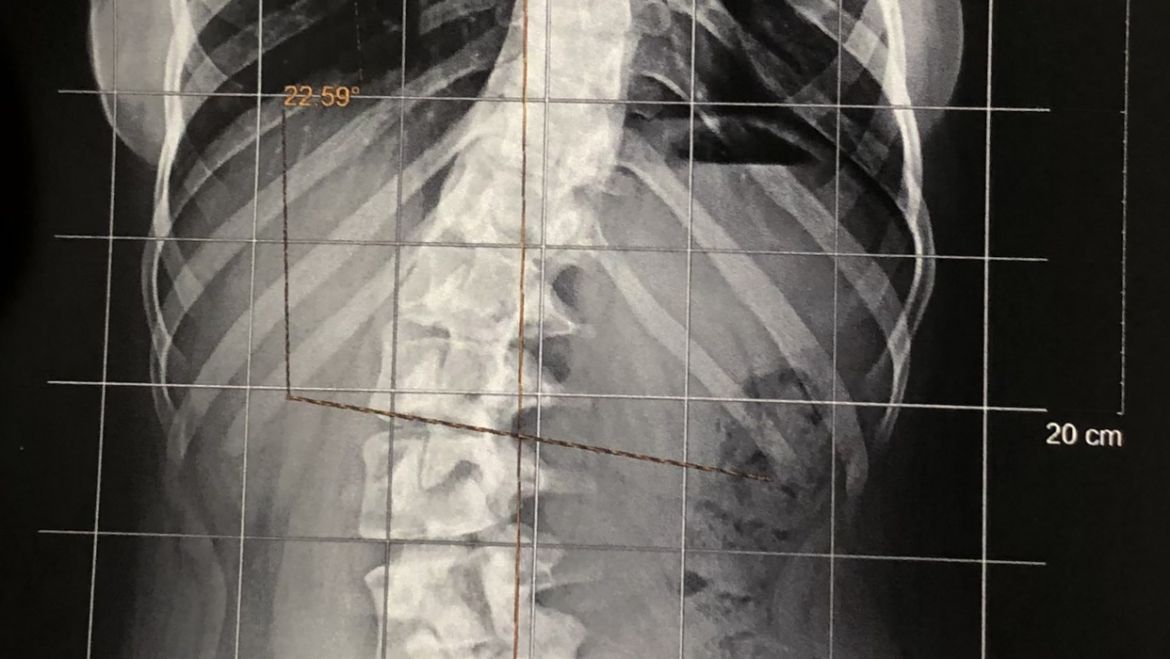

A escoliose é uma alteração em que ocorre curvatura lateral da coluna, como mostrado na imagem. Existem várias formas de escoliose, decorrentes de várias causas. A mais comum delas é a chamada de escoliose idiopática adolescente. Nessa doença, ainda não há um causa bem estabelecida para sua ocorrência (por isso chamada de idiopática) e ocorre na faixa etária da adolescência (acima de 10 anos), como especifica o nome. Afeta homens e mulheres de forma estatisticamente semelhante, porém o risco de progressão e necessidade de tratamento é 10x maior em mulheres. bh

O paciente com escoliose adolesecente pode sentir dores na coluna ou não sentir nada. A inclinação do tronco pode ser visível a olho nu ou, em casos mais leves, somente notada através de avaliação especializada. Em curvaturas maiores, além de dor nas costas pode ocorrer importante incômodo estético e até mesmo dificuldade para respirar. bh

A indicação do tratamento para escoliose vai depender de vários fatores, principalmente, o grau de curvatura, a idade, o desenvolvimento puberal e a maturidade óssea. Pacientes com curvas maiores e menor maturidade óssea (pré menopausa) tem maior risco de progressão da curva e devem ser tratados de forma mais criteriosa. ortopedista coluna bh

Entre as opções de tratamento estão o acompanhamento com exame clínico e/ou exames de imagem, o uso do colete e a cirurgia. No geral, pacientes com curvaturas muito pequenas ou com maturidade óssea não precisam de tratamento. Já para aqueles maior grau de curvatura e que não tenham atingido a maturidade óssea é necessário tratamento. ortopedista coluna bh

A cirurgia é indicada para grandes curvaturas ou naqueles pacientes em que a curvatura continua a progredir apesar do uso do colete. ortopedista coluna bh